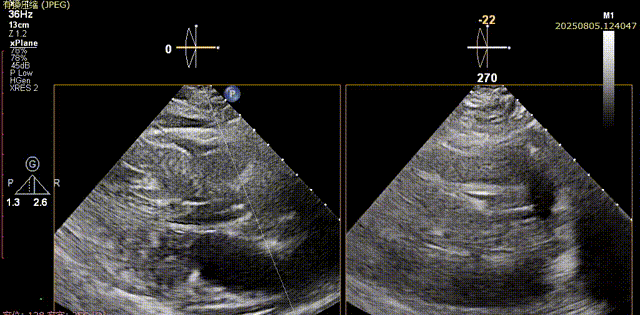

输送器顺利跨瓣,部分释放后,可见喇叭口结构,开始定位释放,180次/分起搏下展开至工作位,超声评估可见位置可,二尖瓣活动良好,瓣周反流较少,综合考虑瓣膜锚定良好,脱钩释放

输送器跨瓣

瓣膜展开至工作位

工作位评估1

工作位评估2